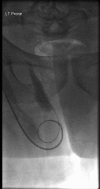

We report 2 cases of inguinoscrotal hernias involving urologic organs. The first case involved an elderly gentleman with a history of micturition by squeezing his scrotum. He was diagnosed as having a right-sided indirect inguinal hernia involving the right ureter and bladder. Treatment was surgical. The second case involved an achondroplastic male who presented with acute kidney injury. He had bilateral hydronephrosis and ureteric obstruction secondary to an ureteroinguinal herniation bilaterally. The presentation, diagnosis, and treatment of inguinoscrotal hernias involving the bladder and ureters are discussed.